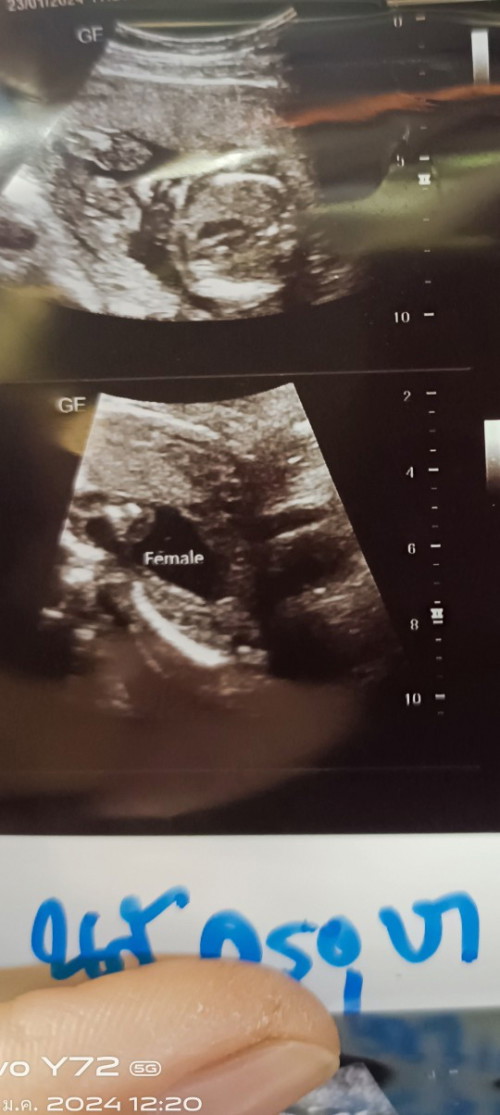

คือแม่บ้านนี้แอบไปซาวด์เพศลูกที่คลีนิคมา หมอบอกน้องเป็นผู้หญิง เลยอยากเห็นรูปซาวด์ของแม่ๆบ้านอื่นว่าเป็นเหมือนกันไหมค่ะ แม่อยากมั่นใจ555 #ขอบคุณล่วงหน้าสำหรับความคิดเห็นค่ะ

บ้านนี้หมอที่ รพ บอกผู้หญิง แม่ไปซาวด์ที่คลินิกหมอก็บอกผู้หญิง ส่วนตัวแม่อยากได้ผู้หญิงอยู่แล้ว แต่แม่ก็ยังไม่มันใจค่ะ ทีม มิถุนายน จร้า